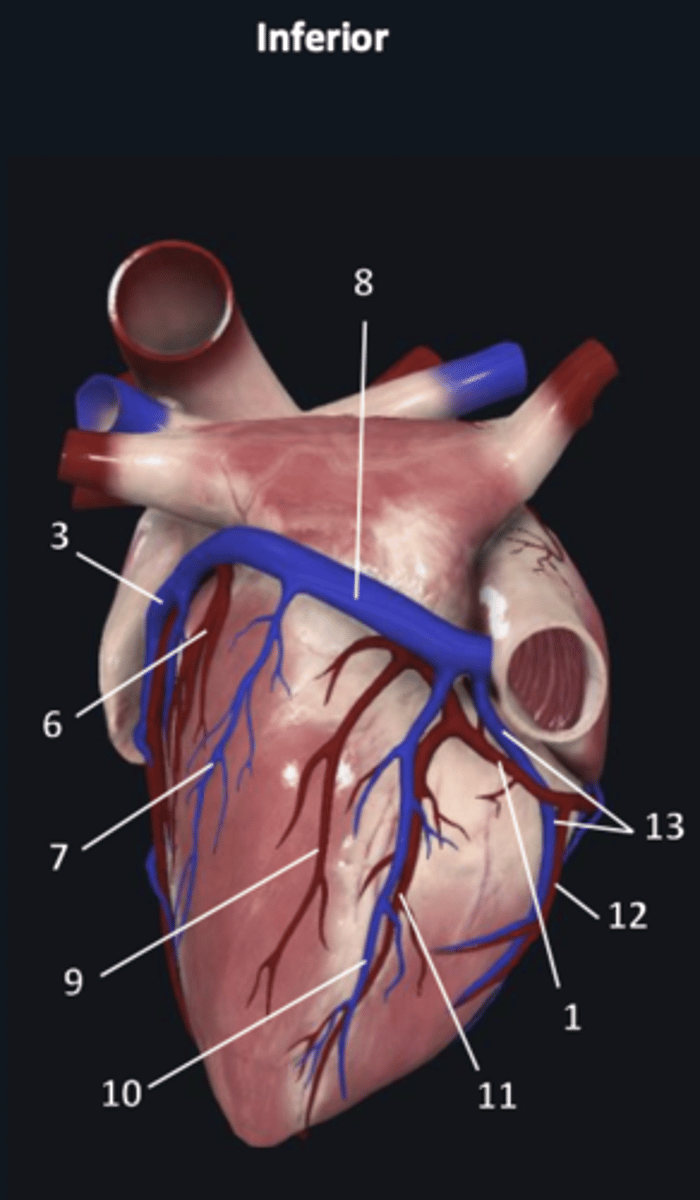

right coronary artery

1

anterior interventricular artery

2 (red)

great cardiac vein

3 (blue)

anterior interventricular artery

2 (red)

great cardiac vein

3 (blue)

left marginal artery

4

left marginal vein

5

posterior left ventricular artery

6

posterior vein of left ventricle

7

coronary sinus

8

right coronary artery

1 (red)

great cardiac vein

3

posterior left ventricular artery

6

posterior vein of left ventricle

7

coronary sinus

8

right posterolateral artery

9

middle cardiac vein

10

posterior interventricular artery

11

right marginal artery

12

small cardiac vein

13